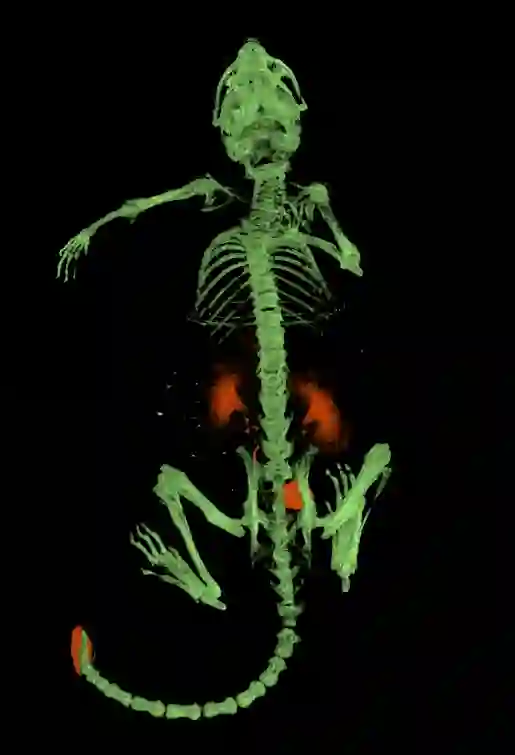

应用一:小鼠注射低浓度碘海醇后吸收边成像的结果,图中橙色为碘元素,绿色为骨骼。